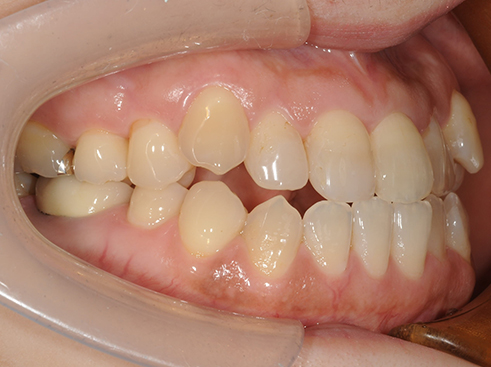

『出っ歯』や『受け口』、『すきっ歯』だって矯正治療で治せます

出っ歯や受け口は見た目や噛み合わせだけでなく、将来の歯の寿命にも関係してきます。

良い噛み合わせはあなたの歯を守ります。矯正は噛み合わせのバランスや力のコントロールを整え歯を長持ちさせる治療でもあります。

<受け口を治療した症例>

治療前

治療後